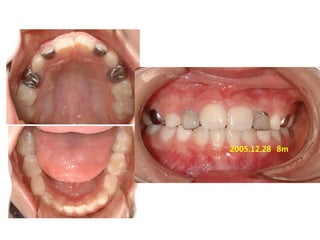

1998 02 .24/ F

C.C

• Crooked upper ant.

Dx

• Lack of space

Goal

• Establish normal tongue posture

2005.01.07

2005.04..28 Tr start

2005.12.28 8m

2007.01.04 1y 8m

2007.07.27 2y3m

2008.05.10 3y